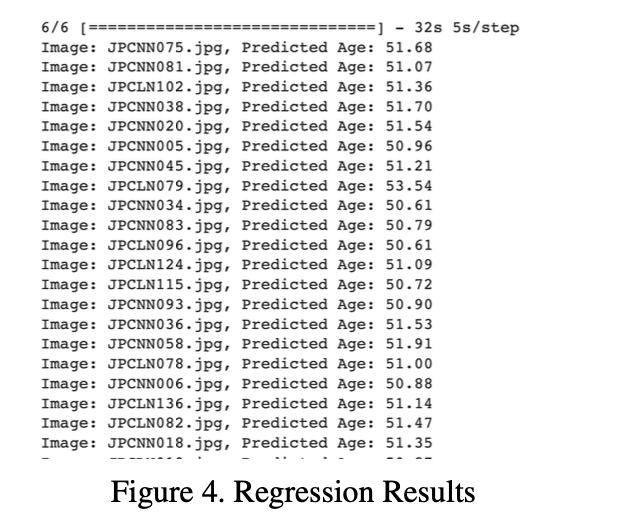

对于每张图像,都会打印相应的预测年龄以进行随机评估:

在初始时期(纪元 1/10),模型开始时的训练损失相对较高,约为 2898.96,验证损失约为 2692.35。

随后的 epoch 显示训练和验证损失持续减少,表明模型能够从数据中学习和泛化。在训练结束时,该模型的训练损失约为 243.32,验证损失约为 229.69。

验证损失: 以 MSE 衡量的验证损失是模型在年龄估计中准确性的关键指标。训练结束时大约229.69的验证损失表明该模型能够根据胸部X射线图像做出相当精确的年龄预测。

在整个训练过程中损失值的降低表明了该模型对年龄估计任务的有效学习和适应。